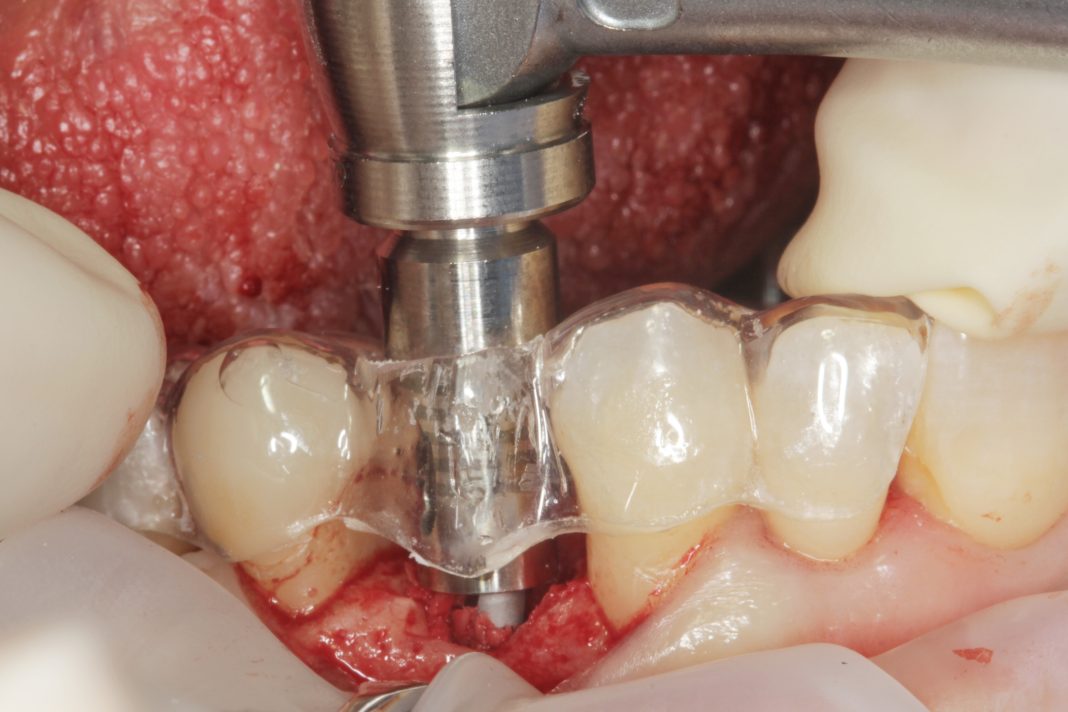

La pianificazione preoperatoria virtuale ha incluso la scansione intraorale e la CBCT. Con i dati raccolti sono stati generati modelli virtuali altamente precisi dell’anatomia del paziente ed è stata pianificata la posizione ideale degli impianti. In base a questa pianificazione sono state prodotte dime chirurgiche CAD/CAM per replicare la posizione e l’angolazione implantare pianificate. Le dime sono state fatte calzare sui denti adiacenti, incorporando i driver statici coerenti con il manipolo chirurgico utilizzato dall’operatore (Figura 1).

Grazie a dima e drivers, la chirurgia guidata consente una fresatura biologicamente incrementale come con un protocollo convenzionale; l’osso autologo raccolto durante la fresatura può essere utilizzato come particolato da innesto al bisogno. I dati clinici e demografici raccolti includono età, sesso, storia clinica e terapie farmacologiche in atto. I dati correlati agli impianti includono, invece, localizzazione anatomica, diametro, lunghezza, torque di inserzione, tipo di protesi, e parametri ossei rilevati alla diagnosi (Figure 2-3). Nel corso del follow-up sono stati registrati la sopravvivenza implantare protesica e il livello di osso marginale. I dati sono stati registrati da un esaminatore indipendente.